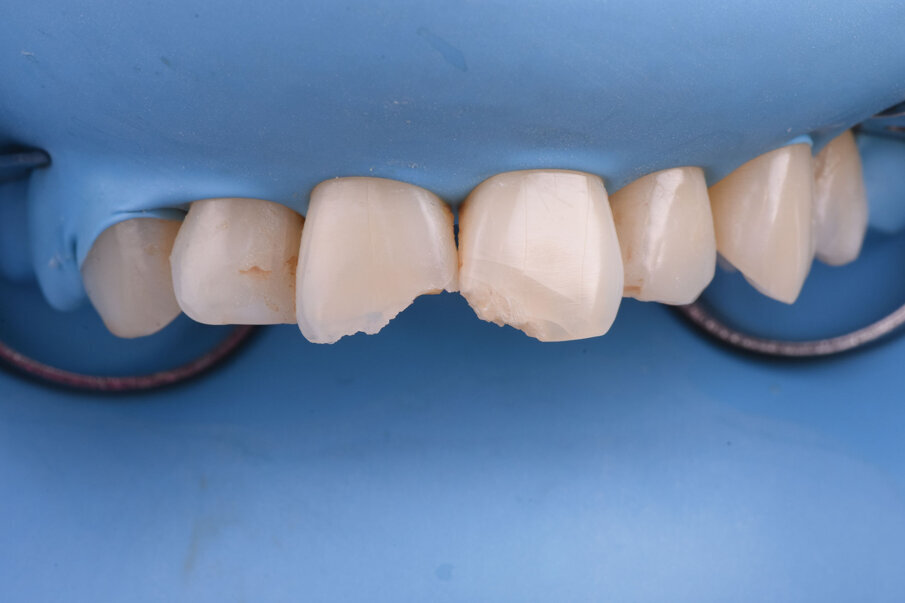

Sl. 1: Inicijalna situacija. Fraktura gornjih centralnih inciziva sa povredom mekog tkiva usne i brade

Sl. 2: Pozicija frakturiranih zuba u maksimalnoj interkuspaciji

Sl. 3: Palatinalni prikaz frakturne linije